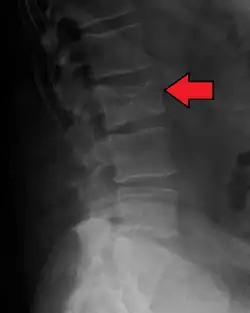

Illustration showing the most common site of bone lesions in vertebrae

Bone pain affects almost 70% of people with multiple myeloma and is one of the most common symptoms.[2]: 653 [23] Myeloma bone pain usually involves the spine and ribs and worsens with activity. Persistent, localized pain may indicate a pathological bone fracture. Involvement of the vertebrae may lead to spinal cord compression or kyphosis. Myeloma bone disease is due to the overexpression of receptor activator for nuclear factor κ B ligand (RANKL) by bone marrow stroma. RANKL activates osteoclasts, which resorb bone. The resultant bone lesions are lytic (cause breakdown) in nature. They are best seen in plain radiographs, which may show "punched-out" resorptive lesions (including the "raindrop" appearance of the skull on radiography). The breakdown of bone also leads to the release of calcium ions into the blood, leading to hypercalcemia and its associated symptoms.[24]

The diagnostic examination of a person with suspected multiple myeloma typically includes a skeletal survey. This is a series of X-rays of the skull, axial skeleton, and proximal long bones. Myeloma activity sometimes appears as "lytic lesions" (with local disappearance of normal bone due to resorption) or as "punched-out lesions" on the skull X-ray ("raindrop skull"). Lesions may also be sclerotic, which is seen as radiodense.[76] Overall, the radiodensity of myeloma is between −30 and 120 Hounsfield units (HU).[77] Magnetic resonance imaging is more sensitive than simple X-rays in the detection of lytic lesions. An MRI may supersede a skeletal survey, especially when vertebral disease is suspected. Occasionally, a CT scan is performed to measure the size of soft-tissue plasmacytomas. Nuclear Medicine Bone scans are typically not of any additional value in the workup of people with myeloma (no new bone formation; lytic lesions not well visualized on nuclear bone scan).